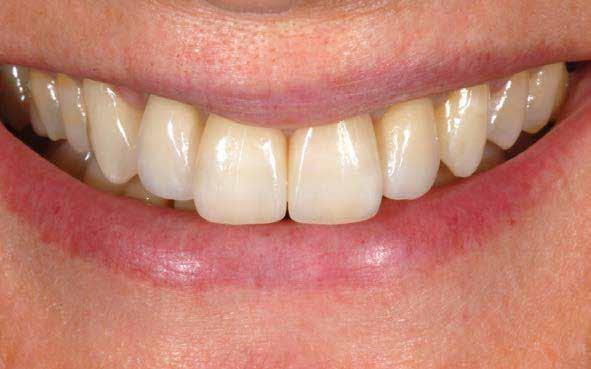

ÚJ PARADIGMA AZ ESZTÉTIKAI HELYREÁLLÍTÁSBAN

Fontfogak esztétikai helyreállítása KATANA™ UTML teljesen anatómikus koronákkal, vesztibuláris leplezéssel és Biológiailag

Dr. Marco Nicastro (Olaszország) A kiindulási állapot és a végeredmény. A KATANA™ UTML kiváló esztétikai tulajdonságokkal rendelkezik, és tökéletesen, harmonikusan illeszkedik a rózsaszín szövetekkel.

1. ábra: A beteg esztétikai problémájára kért megoldást a régi restaurációk természetellenes megjelenése, továbbá a múltban lezajlott periodontitis következtében kialakult fekete háromszögek miatt. A szövetek visszahúzódása következtében a fogpótlás széle jól láthatóvá vált, a papilla csúcsok elvesztése és a koronák közötti számos fekete térrel együtt, komplex terápiás ellátást igényelt.

16. ábra: Klinikai fotó egy évvel a PANAVIA V5-tel történő beragasztás után. A marginális szövetek jó klinikai állapotát látjuk, semmi jele gyulladásnak vagy vérzésnek. A BOPT lehetővé teszi számunkra, hogy optimalizáljuk a gingiva szintjét anélkül, hogy parodontológiai sebészeti beavatkozáshoz folyamodnánk, miközben az új koronák alakja lehetővé tette az interproximális terek zárását az optimális esztétikai eredmény érdekében.

17. ábra: A fogpótlás világossága (főleg a transzlucentes cirkónium használatának köszönhetően), a metszők alakjával kombinálva nagymértékben javította a pótlás esztétikáját, még akkor is, ha a kiindulási helyzet különösen kedvezőtlennek tűnt.

18. ábra: Az előző fogpótlással összehasonlítva a metszők redukálása nem csak azt tette számunkra lehetővé, hogy optimalizáljuk a funkcionális fázist az overjet csökkentésével, hanem lehetővé tette a még esztétikusabb eredmény elérését azzal, hogy a metszők élének kontúrjával követni tudtuk az alsó ajkat.